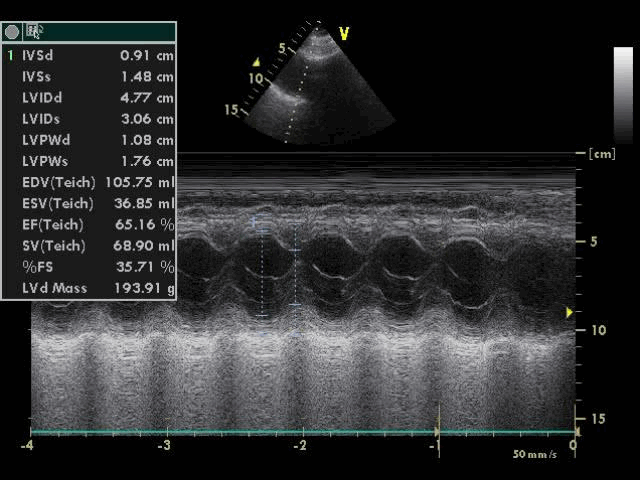

Отмечались признаки умеренной легочной артериальной гипертонии, (систолическое давление в легочной артерии 47 мм.рт.ст.). Визуализация створок и подклапанных структур митрального клапана при трансторакальной ЭхоКГ была недостаточно информативной. В связи с этим потребовалось выполнение чреспищеводной ЭхоКГ, при которой была подтверждена выраженная митральная регургитация, обусловленная полным отрывом головки переднелатеральной папиллярной мышцы и пролабированием ее и передней створки митрального клапана в полость левого предсердия (рисунки 4 и 5).

| Рисунок 4. Чреспищеводная ЭхоКГ, 2-х камерная верхушечная позиция: пролабирование передней створки митрального клапана с папиллярной мышцей в полость левого предсердия | Рисунок 5. Чреспищеводная ЭхоКГ, 4-х камерная верхушечная позиция, цветовое допплеровское сканирование: не очень выраженная митральная регургитация |